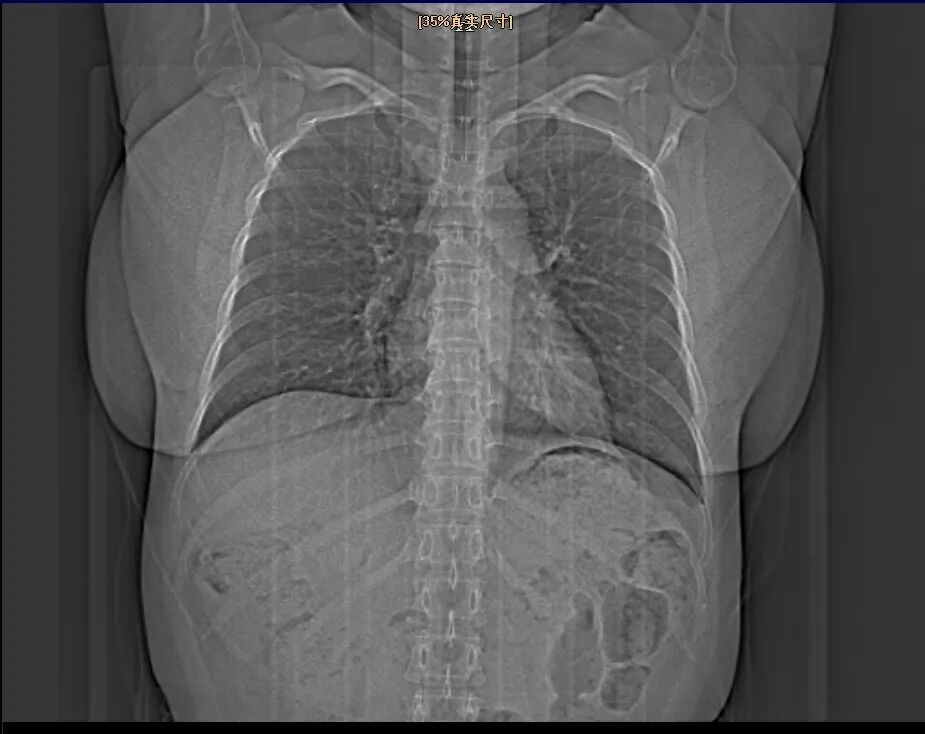

来到义乌市中心医院医学美容中心,科主任虞宏纲为沈女士进行了详细的检查和评估。检查发现,沈女士的双侧乳房明显肥大、下垂,乳房下极超过乳房下皱襞达10厘米以上,乳头位于乳房下皱襞以下,属于典型的巨乳症。

在明确诊断后,医学美容中心团队与浙大一院整形外科副主任、主任医师沈向前教授进行了远程会诊,结合沈女士的乳房大小、下垂程度、身体比例以及个人期望,为她量身定制了个体化的手术方案。

手术当天,沈向前教授与虞宏纲团队配合默契,精准定位、精细操作,共同为沈女士成功实施了双侧缩小型乳房成形术。

整个手术过程顺利。术后即刻效果就非常好,双侧乳房大小适中,形态自然,双侧对称,乳头乳晕位置恢复正常。